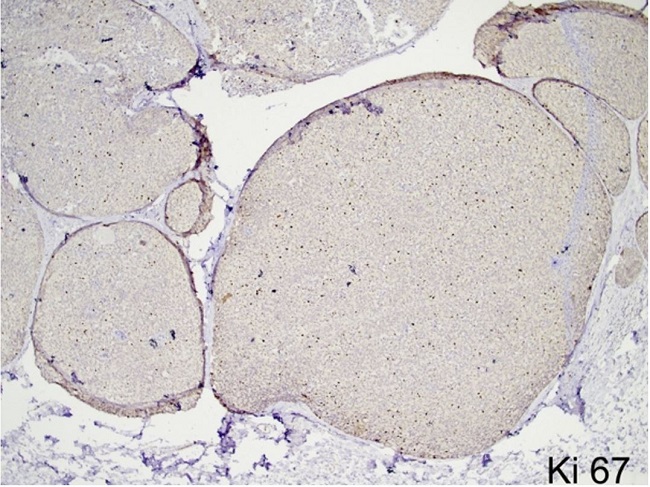

On the immunohistochemical panel reactions, the tumor cells showed strong reactivity for cytokeratin (CK7), synaptophysin, and chromogranin. E-cadherin was retained within the tumor cells. CD34 highlighted the intermixed blood vessels while p63 showed focal loss of myoepithelial cells along with the invasive foci. Breast biomarker studies revealed immunopositivity for estrogen receptor (ER) (Allred score 8/8) and progesterone receptor (PR) (Allred score 8/8), and negativity for Her2 (ASCO/CAP guideline IHC score 0)5 (Figure 3 and 4). The Ki-67 was 15-20% (Figure 5). Hence, a final diagnosis of SPC of the breast (pT2N0) with foci of invasion into the surrounding stroma was rendered. Given the favorable histology and pT2N0 stage, she is currently on adjuvant endocrine therapy.